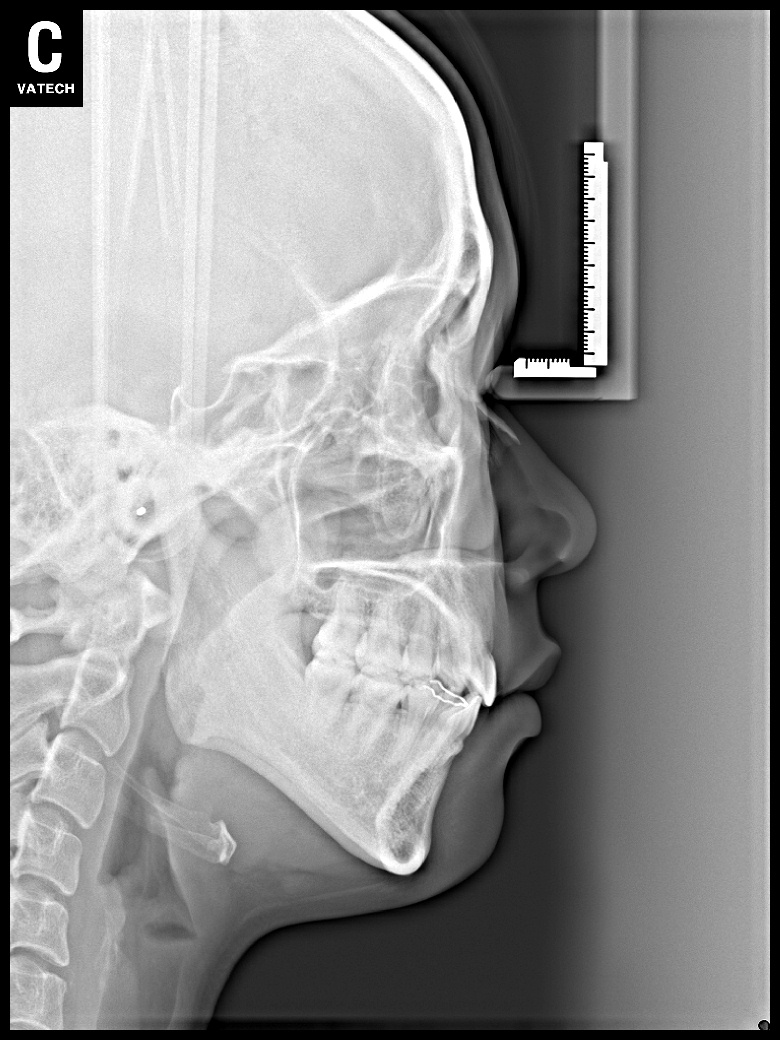

치료 후 사진입니다.